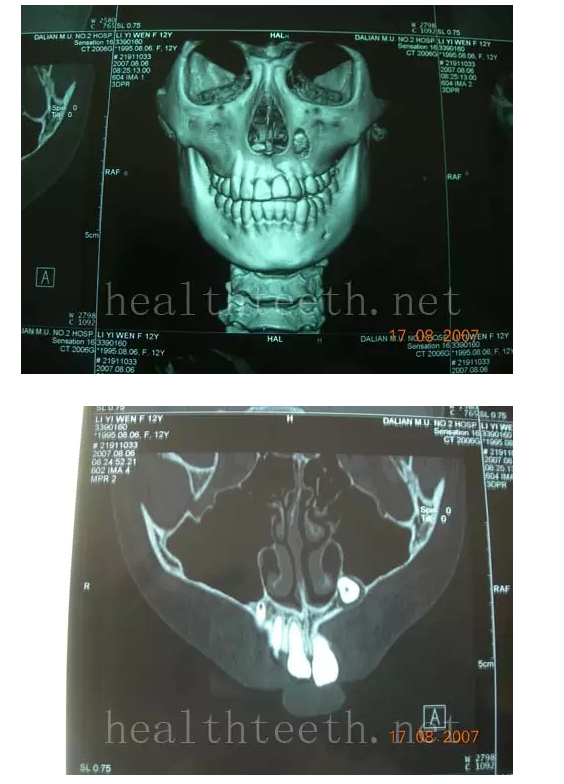

通過CT片確定埋伏牙齒具體的位置,顯示距離左側(cè)上頜竇很近,偏唇側(cè),這為手術(shù)定位提供了方便

手術(shù)中切斷、完整拔出,未損傷上頜竇